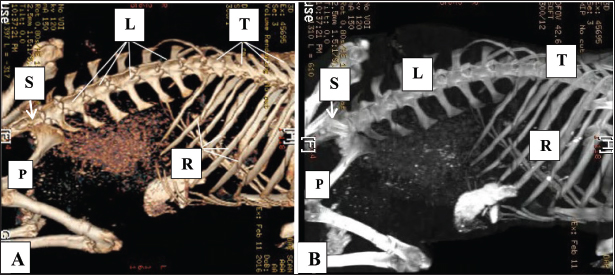

The identification of soft tissue structures on CT was based on their radiostatic density, morphology, and spatial distribution in both the cross-sectional and dorsal plane images. The thoracic and lumbar vertebrae, ribs, and sternum were used as anatomical landmarks to determine the positions of the organs under examination. The bony boundaries of the abdomen and pelvis were demonstrated by 3D CT scan (Fig. 1).

Fig. 1. Normal 3D CT scans of the abdomen and pelvis in healthy goats (Panels A, B) show the thoracic vertebrae (T), lumber vertebrae (L), ribs (R), pelvic bone (P), and sacrum (S).